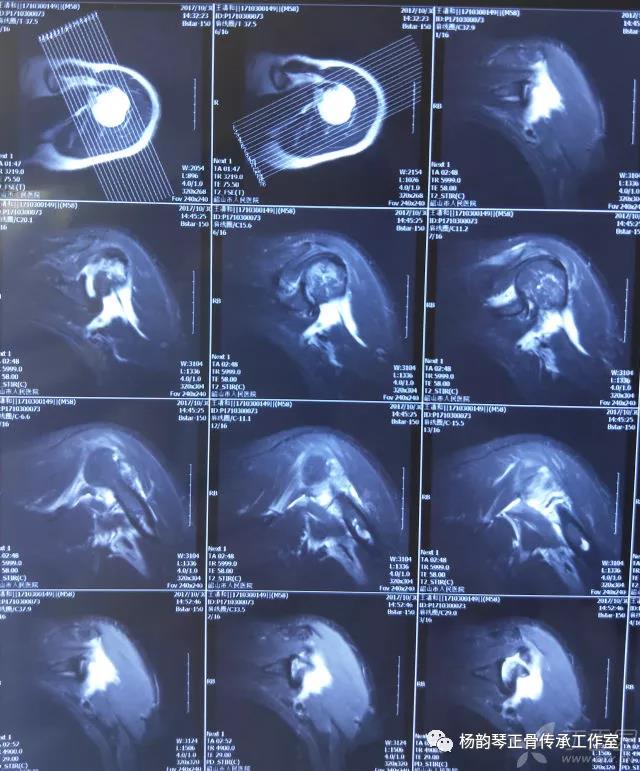

简要病史:骑摩托车跌倒致左肩部肿痛,活动受限,就诊于当地医院,拍片及磁共振检查后诊断为肩袖损伤及肩关节半脱位,予以悬吊固定,因症状缓解不明显就诊于我院。外院拍片情况如下:

应该说是一个典型的“灯泡征”影像,但是并未引起注意。

当地接诊医生应该说还是很负责的,同时拍了健侧片对比:

影像科报告,骨科医生光看报告行吗?

磁共振检查也完善了,还是报了个肩关节半脱位……影像科已经把坑挖好了……

接诊医生直接跳坑里了